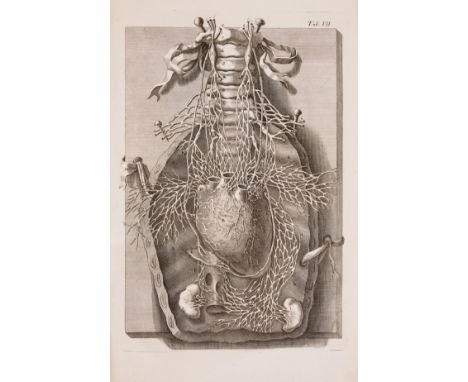

Willis (Thomas) Opera Omnia, engraved additional pictorial title and 37 plates, some folding, lacking portrait, some spotting, engraved title lacking upper outer corner just touching border (repaired), one or two plates torn and repaired, modern morocco-backed marbled boards, Amsterdam, H.Wetsten, 1682 § Motherby (George) A New Medical Dictionary, third edition, 30 engraved plates at end (misbound), a little light spotting or staining, modern morocco-backed cloth, [Wellcome IV.188], J.Johnson, 1791 § Freind (John) Opera omnia medica, first collected edition, initial imprimatur leaf, half-title, engraved portrait and title-vignette, title lightly soiled and with stain to lower outer margin, modern calf-backed marbled boards, spine gilt, [Wellcome III.66], John Wright, 1733, all ex-library copies with traces of stamps to tiles and some plates; and another, 4to & folio (4) ⁂ The first is the third and best edition of the collected works of Willis, a founding member of the Royal Society and a pioneer in research into the anatomy of the brain, nervous system and muscles. The work includes his Cerebri anatome in which he coined the term "neurology". He also discovered the "Circle of Willis", a circle of arteries on the base of the brain.